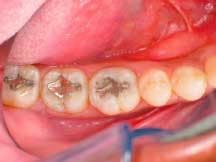

A male patient presented with failing 15-year-old amalgam restorations on Teeth Nos. 17 through 19 (Figure 1) and cold sensitivity on Tooth No. 19. Teeth Nos. 17 and 18 required Class I restorations, while Tooth No. 19 required a Class II restoration. Direct composite resin restorations (4 Seasons Universal Composite and 4 Seasons Flow) were deemed the more appropriate treatment for this patient. This was confirmed following removal of the amalgam restorations, which showed the shallowness of the cavities.

1